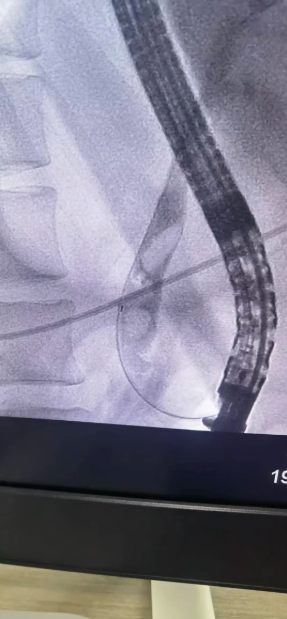

· 精准插管: 在十二指肠镜视野下,专家手法娴熟,一次性成功选择性胆管深插管,为后续操作奠定了坚实基础。

· 巧妙取石: 造影显示,患者胆总管下端有3颗直径约1.5cm的嵌顿性结石。专家采用球囊扩张、网篮取石等一系列高精尖技术,成功将结石完整取出,瞬间,淤积的胆汁顺利引流通畅。

· 鼻胆管引流: 为充分引流、控制感染,术中顺利放置了鼻胆引流管。整个手术流程如行云流水,仅用时不到半小时的时间便宣告成功。患者生命体征平稳,梗阻即刻解除。